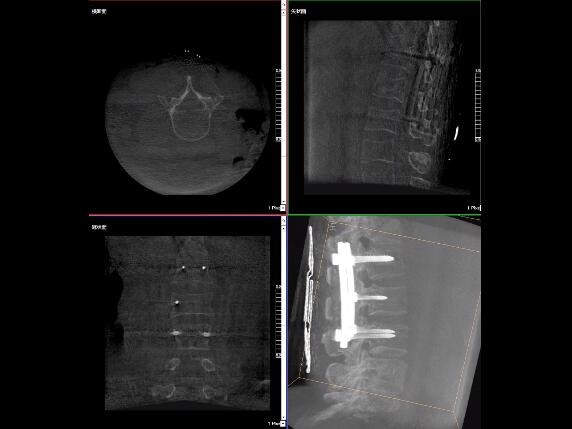

比如,醫(yī)生在做PKP(椎體成形術)的時候,或者在置入螺釘?shù)臅r候,醫(yī)生需要在影像上看到螺釘打進去的進針點以及進針的路徑。比如,我們在打腰椎的釘子時需要看到“貓眼”。我們只有把釘子完全打在“貓眼”里面,才能確保釘子打在了椎弓根里,所以對“貓眼”的顯影就非常重要。

最后我要強調(diào)一點,以上我提到的“貓眼”,在二維的X光片上,醫(yī)生是靠經(jīng)驗去判斷釘子是否打在椎弓根里,這個時候如果我們的設備再先進一點,診斷手段再多一點,如果我們能夠把二維的影像轉(zhuǎn)換為三維的影像,可能就不會完全依賴醫(yī)生的經(jīng)驗。

我們可以在三維的圖像中直觀的看到釘子到底在不在椎弓根里面,這樣可以指導我們準確的進針,指導我們進行一場高質(zhì)量的手術,可以起到事半功倍的效果,手術會簡單得多,病人的預后也會好得多。